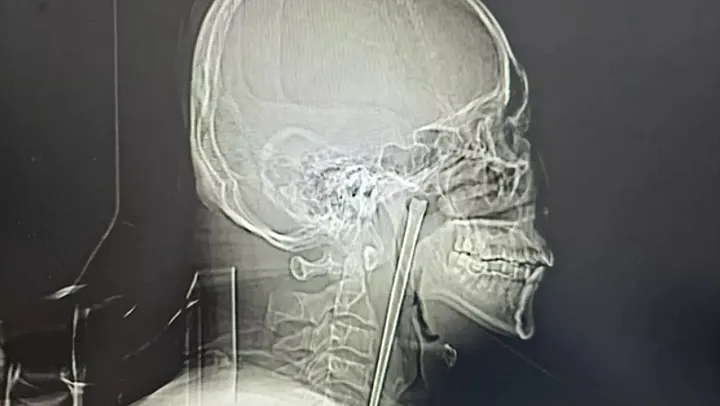

Aradan geçen yıllar boyunca boğazındaki yabancı cisim hissini 'katlanılabilir' bulan Wang, son dönemde şiddetli ağrıların başlamasıyla Dalian Üniversitesi Teknoloji Hastanesi'ne başvurdu. Yapılan ilk fiziki muayenede herhangi bir enfeksiyon izine rastlanmasa da çekilen röntgen filmi korkunç gerçeği ortaya çıkardı: Boğaz dokusunun iç kısımlarına yerleşmiş, hayati damarların hemen yanında duran 12 santimetrelik dev bir metal şaft.

Dr. Huang Weipeng ve ekibi, hayati damarlara zarar vermemek adına oldukça hassas bir operasyon planladı. Kapalı cerrahi yöntemiyle ağız içinden gerçekleştirilen müdahale sonucunda, yıllardır orada duran paslanmaz çelik çubuk tek parça halinde dışarı çıkarıldı. Operasyonun ardından sağlığına kavuşan Wang'ın tüm ağrıları sona erdi. Uzmanlar, bu tür durumlarda 'vakit kaybetmeden' tıbbi yardım alınması gerektiği, aksi halde doku tahribatı ve ölümcül kanamaların kaçınılmaz olduğu konusunda uyardı.